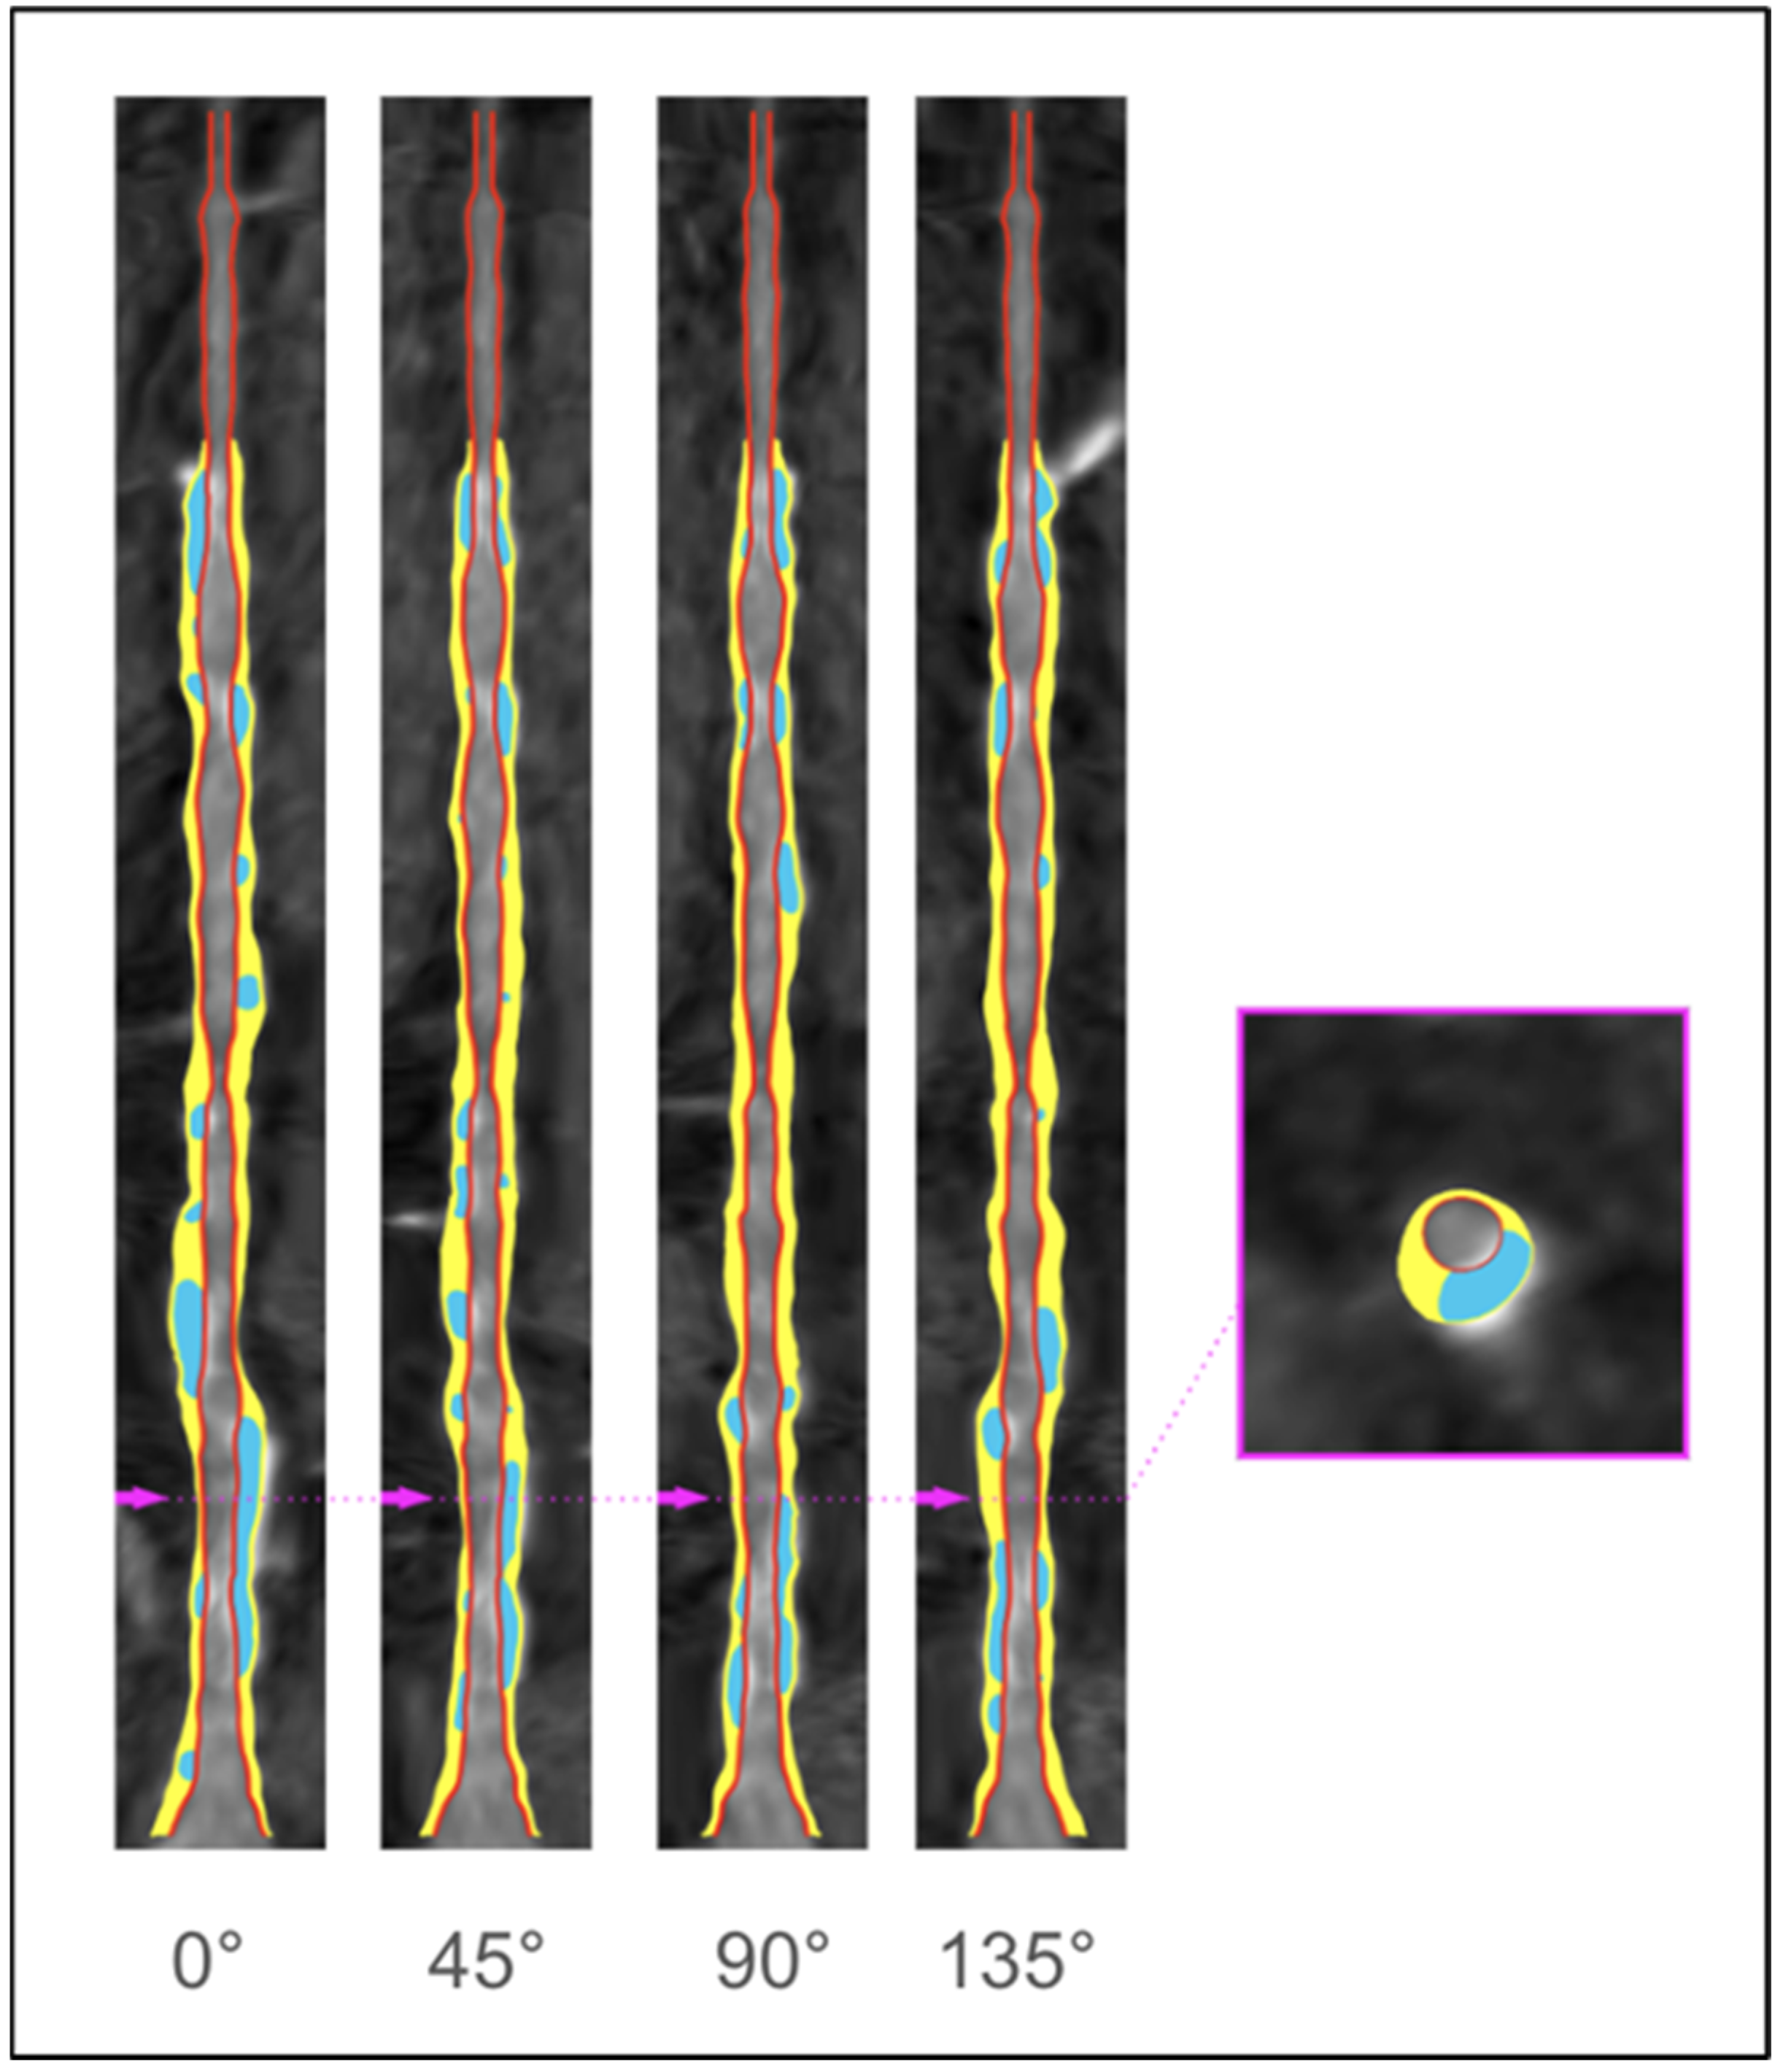

2. Anatomical Evaluation of Coronary Arteries

7.5. Chronic Total Occlusion (CTO)